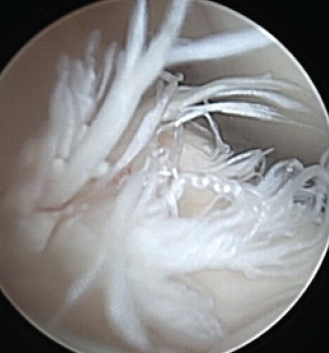

Arthrex Labral Scorpion for Anterior Cruciate Ligament Repair: A Novel Application for this Instrument: Case Report

Vanessa C Heck , Logan Van Poucke , Holly C Heck , Alex D Keith , Brian Holmes , Bruce E Heck

………………………………p.75-81